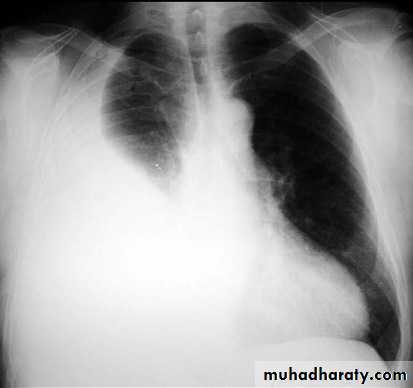

Pleural effusionPleural effusion tends to be used as a catch-all term denoting a collection of fluid within the pleural space. This can be further divided into exudates and transudates depending on the biochemical analysis of aspirated pleural fluid. Essentially it represents any pathological process which overwhelms the pleura's ability to reabsorb fluid.

Plain radiographChest radiographs are the most commonly used examination to assess for presence of a pleural effusion, however it should be noted that on a routine erect chest x-ray as much as 250-600 ml of fluid is required before it becomes evident 6. A lateral decubitus film is most sensitive, able to identify even a small amount of fluid. At the other extreme, supine films can mask large quantities of fluid.

Both PA and AP erect films are insensitive to small amounts of fluid. Features include:

blunting of the costophrenic angle

blunting of the cardiophrenic angle

fluid within the horizontal or oblique fissures

eventually a meniscus will be seen, on frontal films seen laterally and gently sloping medially (note:

with large volume effusions, mediastinal shift occurs away from the effusion (note: if coexistent collapse dominates then mediastinal shift may occur towards the effusion)